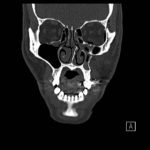

Physical exam showed marked left palpebral subcutaneous crepitus, as well as bulbar and palpebral conjunctival bulging. Visual acuity was normal with intact extraocular movements, and normal pupillary exam. Computed tomography (CT) imaging of the face was obtained and revealed multiple displaced fractures involving the left orbital floor and zygomatic arch associated with moderate periorbital and postseptal extraconal gas, resulting in orbital proptosis.